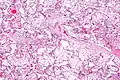

| Micrograph of villous immaturity. H&E stain. | |

Immature chorionic villi are larger and have more central blood vessels; thus, the diffusion distance for gas and nutrient exchange is larger and, therefore, placental function is impaired.

Low mag.